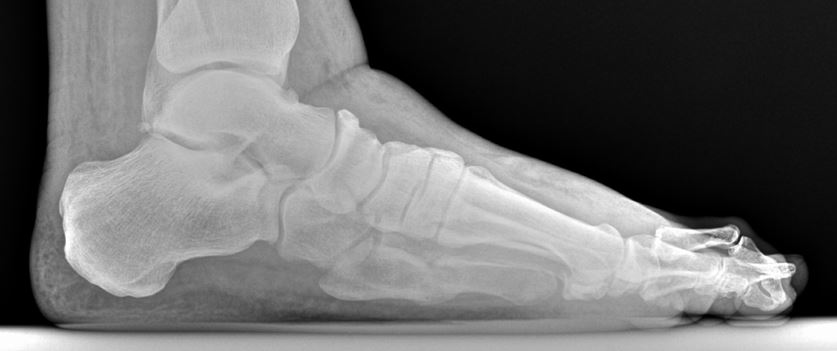

Weird case. 50ish year old male. I actually found this looking back through x-rays the other day. The guy had seen another DPM or ortho less than a year before for problems with the 5th metatarsal. He always had lingering issues even after it "calmed" down. Walked in acutely tender/painful/swollen with no protection or anything like that. Active smoker. History of a DVT. Scheduled for a major gastrointestinal surgery that he was literally flying to the other side of the country for. We came in and discussed a variety of options which I won't write to leave it open to discussion. Anyway. Sadly, he died a few months after the other surgery.

Questions you could ask yourself about the fracture - what are fracture findings of healing? What are clinical findings of healing? Does this fracture look - irregular? When is a fracture a non-union? What issues are raised by recurrent fractures of the lateral foot?

How about that 2nd MPJ?

-On the lateral you can see the toe raised above the plane of the other toes. Now that can occur without subluxation of the MPJ ie. contracture within the joint; however, it does appear more dorsal at the MPJ itself.